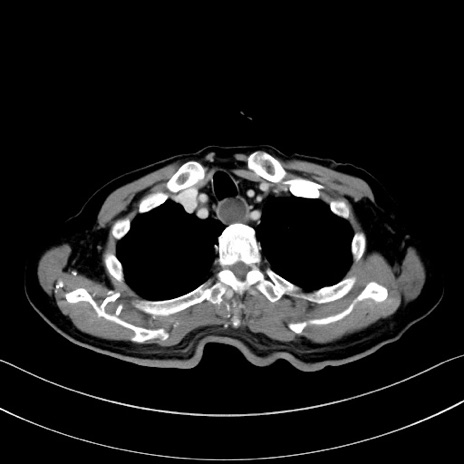

症例28(横断像)

【症例】60歳代男性

【現病歴】胃癌にて胃全摘後。食思不振が悪化し、夜中に嘔吐することがある。

【既往歴】胃癌、胃全摘、脾摘、胆摘後